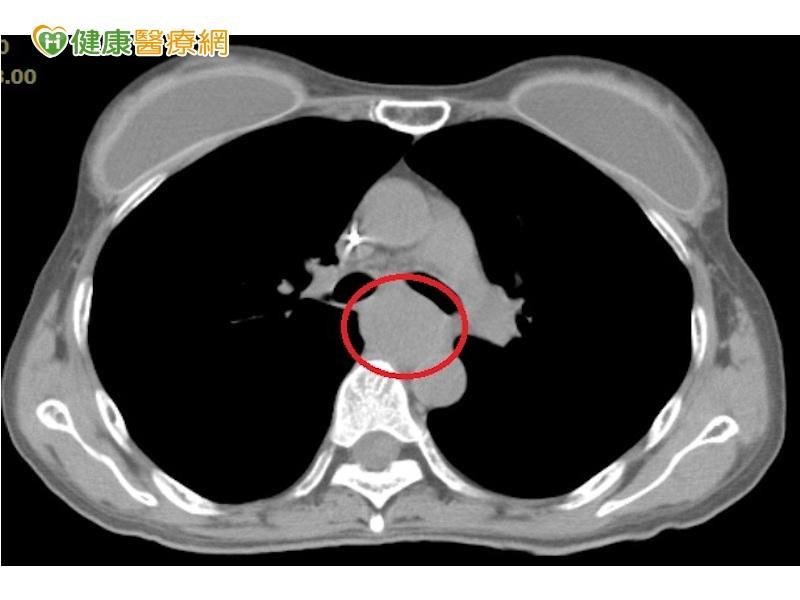

抽菸喝酒對於健康的危害不可小覷!一名45歲女性,因工作緣故經常會喝酒抽菸,某次突然發現自己吞嚥困難,起初以為是喝烈酒灼傷喉嚨,後來卻連喝水都有困難,但她卻拖了三個月,因為胃痛掛急診時,進一步檢查而確診為罹患第四期食道癌。

食道癌阻塞食道 改採光子刀放射治療

臨床上,晚期發現的食道癌較少見,這名患者食道癌約2公分×10公分,佈滿食道的中上段,病理切片化驗確診為鱗狀上皮細胞癌;收治這名女子的澄清醫院中港院區放射腫瘤科主治醫師梁家郡指出,患者食道已完全阻塞,癌細胞雖無遠端轉移,但因局部侵犯到氣管,已無法開刀治療,只好採以光子刀放射治療,透過二十二次的光子刀放射治療,讓癌腫瘤萎縮後,再配合化療,目前患者食道癌已縮小二分之一,可免強嚥食喝水,維持生命養分。